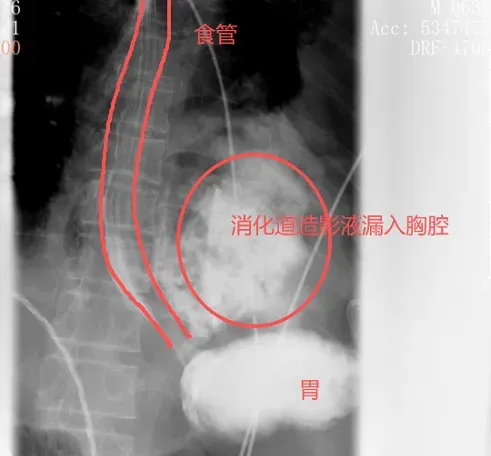

很快,口服钡餐的结果印证了他的判断:钡剂从食道下段的裂口处大量漏出,直接进入了左侧胸腔。

自发性食管破裂,也称为Boerhaave综合征,是胸外科最凶险的急症之一,发病急、进展快、死亡率极高。而此时,距离张叔发病还不到24小时——这是救治的黄金窗口期。

“这个病,最关键的从来都不是手术,而是及时确诊。只要诊断明确了,后续的治疗就有方向了。”刘继先主任解释,一旦超过24小时,食道管壁会严重水肿、糜烂,变得像泡发的棉花套一样,根本无法缝合修补。